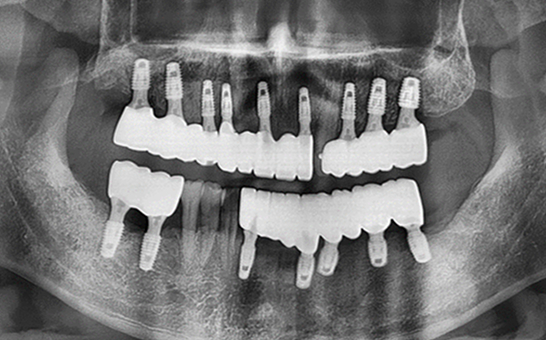

바른선택치과의원 전악 임플란트

치료 시작 전 촬영 2024.01.24 | 치료 완료 후 촬영 2024.12.26

CASE 01 김** / 60대

전악임플란트

1 예후불량 치아 발치

2 발치 후 즉시 임플란트 식립 및 뼈이식

3 고정성 보철물로 수복 후 일상 회복